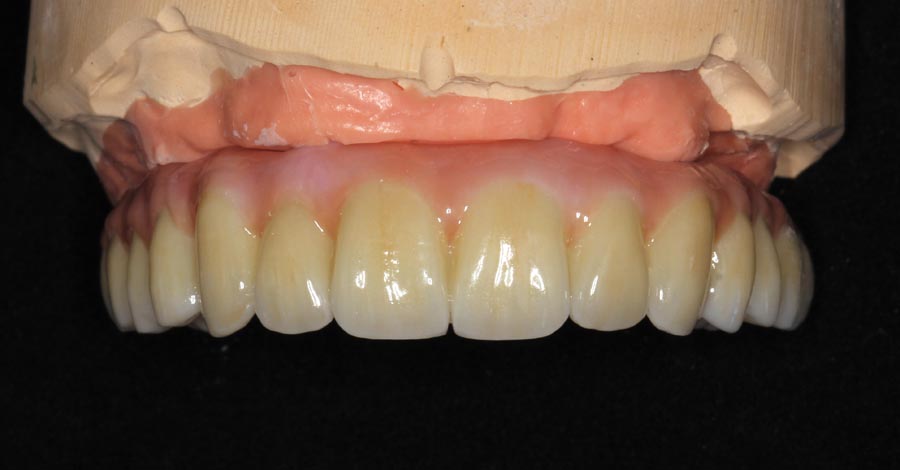

Matching of the gum tissue color is one more step we take in the “customization” process. Most offices have only two choices for the gum color.

Tissue-view of the final implant bridge. Note the convex (cleansable) contours. This is a wide departure from “All-on-4” treatment which is virtually uncleansable.